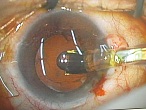

黒目(角膜)から入ってきた光は、目の奥の方のフィルム(網膜)に当たります。網膜は一つの束(視神経)になって、最終的には脳ミソにつながり、「物が見える」という事になります。

図の赤矢印の部分は視神経乳頭と言って、網膜が集まって束になる部分なのですが、実はこの部位のみ光を感じ取ることはできないのです。